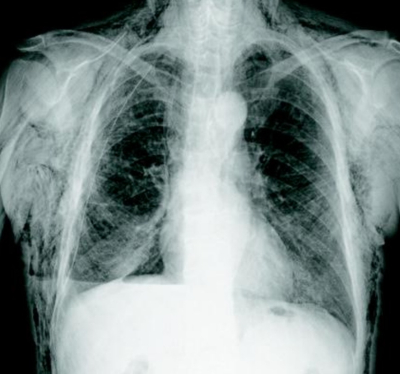

76歳の男性。肺癌治療のため入院中である。根治術として、右肺下葉切除およびリンパ節郭清術を施行された。胸腔ドレーンからの軽度の空気漏れが手術直後から観察されたが、胸部エックス線写真では肺の膨張に問題はなかった。術後3日目、胸腔ドレーンからは依然空気漏れを認めている。手術直後の胸部エックス線写真及び術後3日目の胸部エックス線写真を別に示す。

術後3日後(立位像)